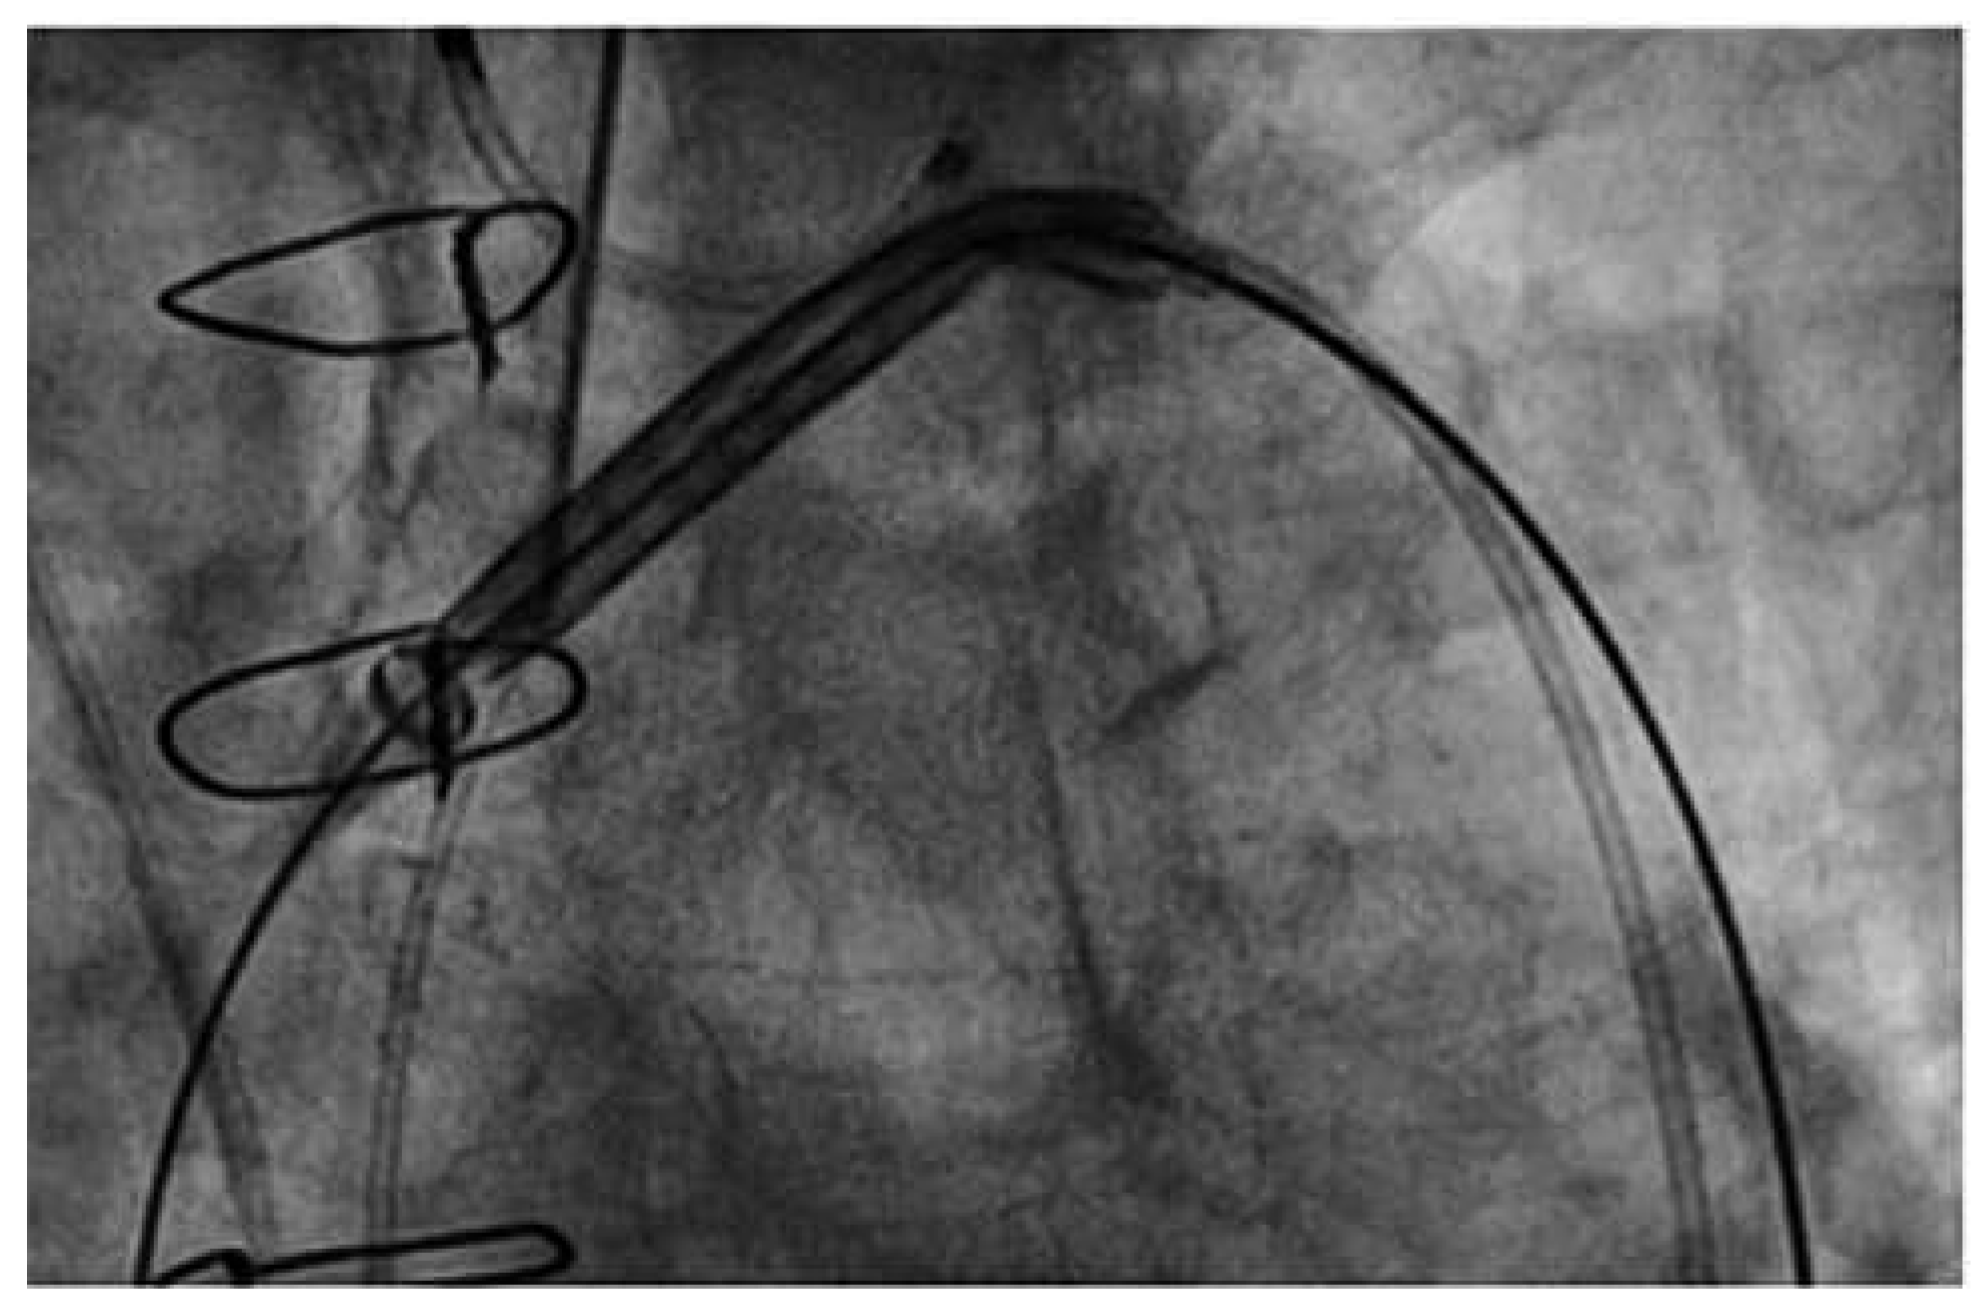

Figure 3. SMT Embolic Deflection Device. The device is introduced by the femoral route. (Courtesy of Keystone Heart Ltd, Herzliya, Israel.).

The EDD (Keystone Heart Ltd, formerly SMT Research & Development Ltd, Herzliya, Israel) is introduced via femoral access (Figure 3). It is a very similar device as the Embrella, also deflecting rather than capturing emboli (Figure 2). However there are some important differences: The device fits through a 7 French sheath, however, a 9 French sheath is often used, to facilitate recapturing of the device and allowing simultaneous placement of a pigtail through the same sheath. The device is self-positioning at the outer curvature of the aortic arch covering all three neck vessels. It is anchored in the brachiocephalic trunk and the inner curvature of the aorta by stabilizing nitinol arms. Femoral access and minimal interference with the brachiocephalic trunk are potentially less traumatic than advancing a device through the brachiocephalic trunk.

The first-in-human experience including 15 patients was presented at TCT 2011 by Dr Pieter Stella, showing a 50% reduction in cerebral embolisation (as assessed by MRI). Given the fact that the deflection device partially protrudes to the aortic lumen, there is a potential for interference of the device with the valve delivery system. This complication, however, was not encountered in the first-in-human experience (personal communication from Dr Stella).